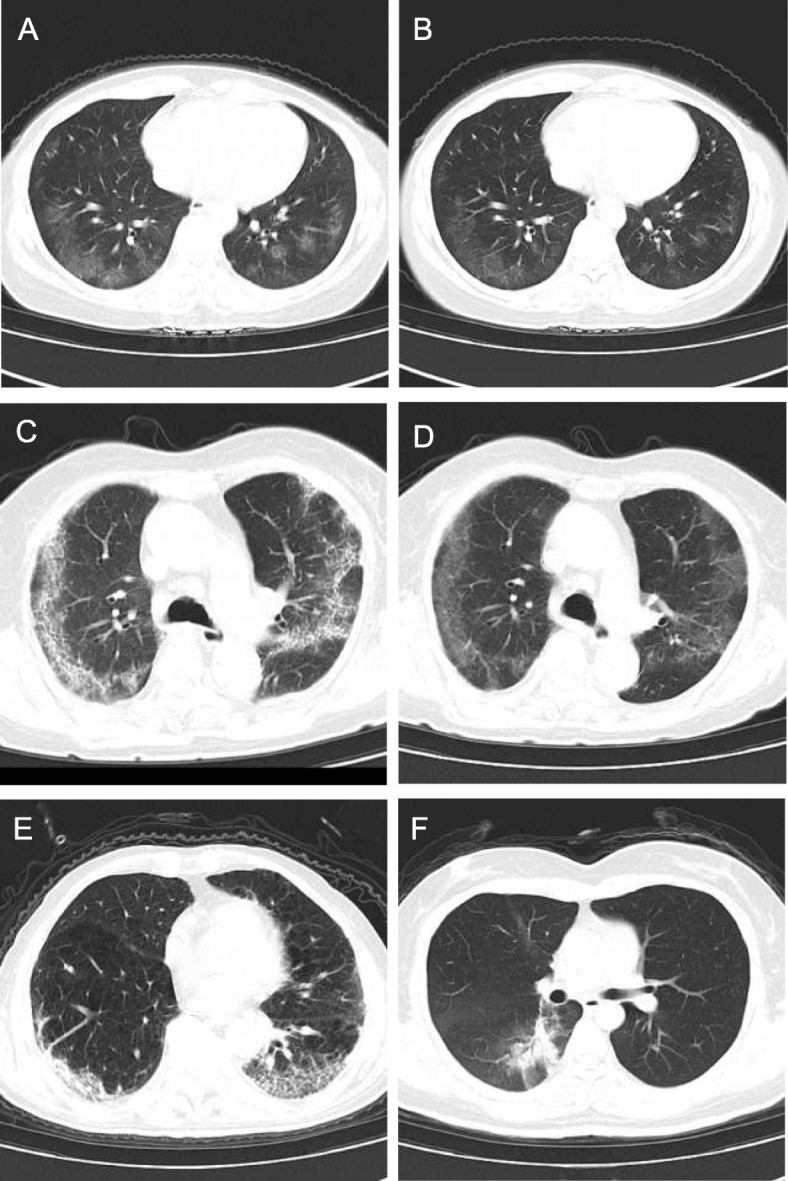

The number of cases with multiple lesions in the study group and control group are 26 and 24, respectively. There were 4 cases with diffusely distributed CT sign in the study group and 6 case in the control group. For cases with mainly subpleural distribution, the number is 28 and 25 for the study group and control group, respectively. There were 2 cases in the study group and 5 cases in the control group were distributed along the bronchial vascular bundle. The main signs of the two groups (Fig. 1 A ~ F) include GGO, crazy-paving pattern, consolidation and fiber cable shadow. A few patients may have axial interstitial thickening. There were no statistical differences in the occurrence rate of the above signs between the two groups (p > 0.05, Table 2).

Fig. 1.

CT images using CareDose 4D combined with Karl 3D technology in the low dose for the follow-up of COVID-19. (A-B) CT images of a 43-year old female. Follow-up with low-dose CT (Fig. A) showed that the lower lobe of the lungs is scattered with thin GGO and the edges are blurred. Tube voltage is 12 0 kV and tube current is 29 mA. After 5 days, follow-up with conventional dose CT (Fig. B), showed slightly absorbed sub-pleural GGO compared to Fig. A. Tube voltage is 120 kV and tube current is 20 mA. (C-D) CT images of a 81-year old female. Follow-up with conventional dose CT (tube voltage of 120KV and tube current of 131 mA) curved grid-like shadows can be seen under the pleura of both lungs, showing crazy-paving pattern (Fig. C), followed by low-dose CT (tube voltage of 20 kV and tube current of 31 mA) follow-up 2 weeks (Fig. D), The symptoms are not obvious, and the arc GGO changes. (E) CT image of a 64-year old male. Low-dose CT follow-up of clearly showed that the lower lobe subpleural crazy-paving pattern and the right lower lung was partially consolidated. (F) CT image of a 38-year old female. Tube voltage 120 kV, tube current 43mAs. Follow-up with low-dose CT showed flaky consolidation in lower lobe of right lung. Dissipative GGO was seen in the surrounding area. Tube voltage is 120 kV and tube current is 33 mA